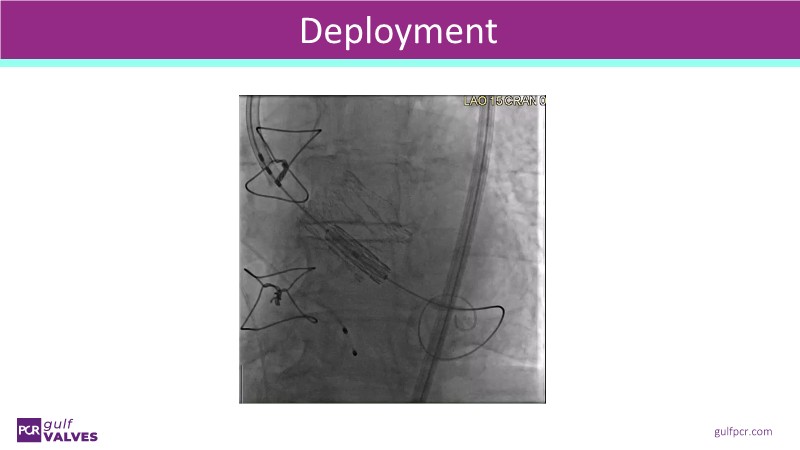

Second valve strategies with SAPIEN 3 Ultra RESILIA

This session helps you anticipate and address complex scenarios such as mitral valve-in-valve, TAV-in-SAV, and valve-in-valve-in-valve procedures. Learn from expert case discussions that explore procedural strategies, technical challenges, and best practices to optimize outcomes in redo structural heart interventions.

- To understand procedural strategies and challenges in complex redo scenarios using SAPIEN 3 Ultra RESILIA